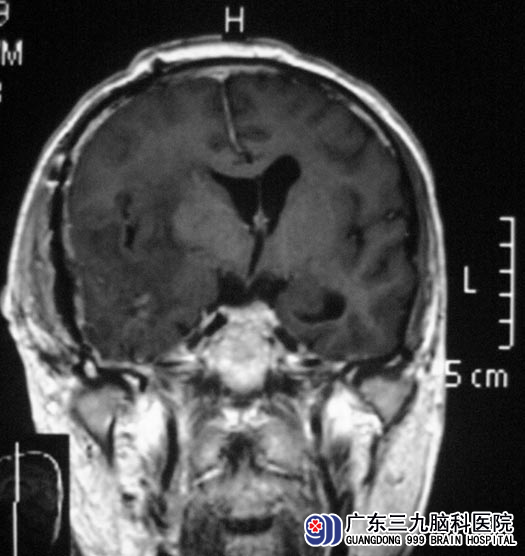

在广东三九脑科医院进一步检查发现:1、右侧颞部占位病灶,考虑血管外皮细胞瘤可能性大,待排间变性脑膜瘤或脑外巨大海绵状血管瘤;2、幕上脑室系统扩大,右侧大脑镰下疝,3、脑白质散在脱髓鞘灶。

5月22日,由综合神经外科 鲁明主任主刀,在全麻下行右侧颞叶占位病变切除术,术中显微镜下见肿瘤紧贴颅底硬脑膜生长,肿瘤表面有大量小血管缠绕,予镜下分块切除,经过顺利。术后康复满意。病理结果为:脑膜瘤(透明细胞型,WHO II级)。